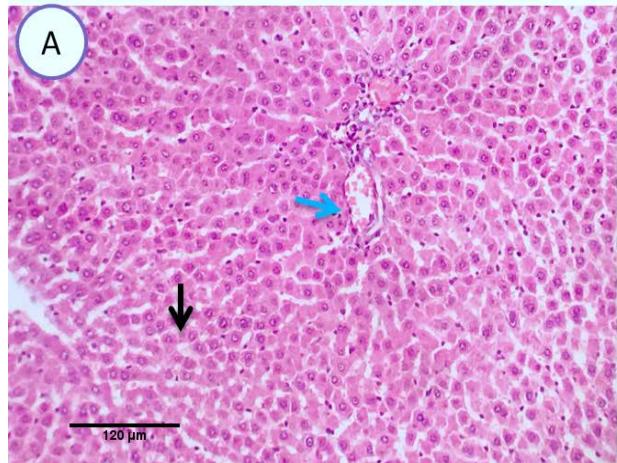

Liver: Examined serial sections from liver revealed normal hepatic parenchyma with preserved lobular pattern, portal triades and associated structures (portal vein, hepatic artery, hepatic vein, bilsductiles and lymphatics). Central vein sinusoids and hepatic cords were apparently normal. Hepaticlobules were separated by fine fibrous stromal connective tissue.(Fig.1).

Fig. 1: Photo-micrograph from liver, control group, showing normal hepatic parenchyma with preserved lobular pattern, central veins (blue arrow), Sinusoids and hepatic cords (black arrow). Scale bars 120, 40 um